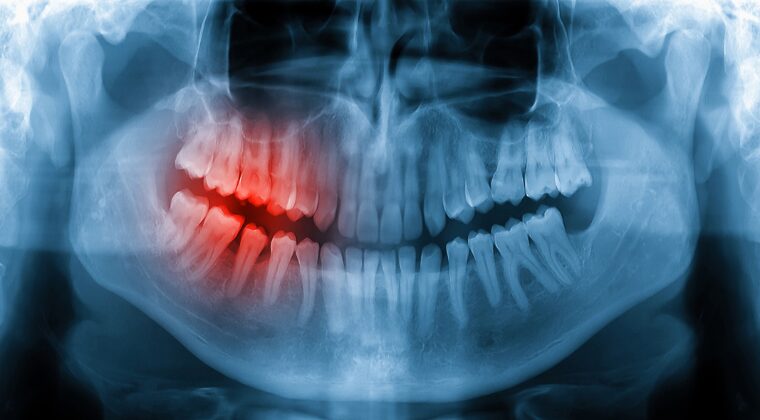

原因3 歯のクッションが炎症を起こす歯根膜炎や歯の破折

歯の根と顎の骨の間には、噛む力を緩衝する歯根膜という組織が存在します。噛み合わせの異常によってこの組織に負荷が集中すると、炎症を起こして強い痛みを伴います。また、負担がかかり続けることで、歯そのものにヒビが入ったり割れたりする破折を引き起こしているケースもあります。